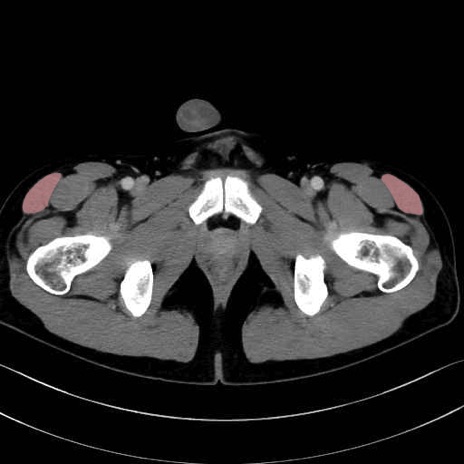

大腿筋膜張筋 (Tensor fasciae latae)